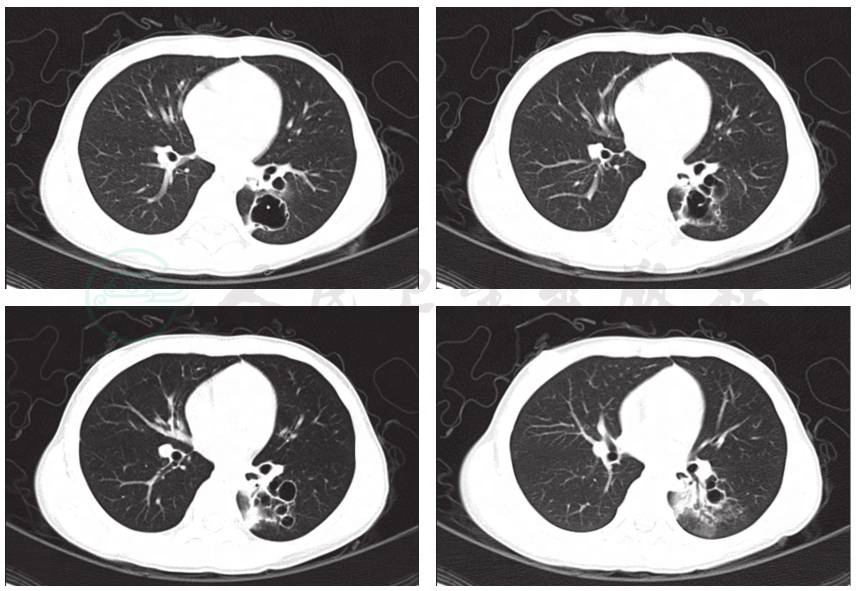

入院后立即予心电、血氧监护,完善相关检查。血常规:白细胞17.2×109/L;中性粒细胞70.8%;血小板496×109/L;红细胞4.6×109/L;血红蛋白132g/L;CRP 45.9mg/L;降钙素原0.15ng/ml。病原学检测:肺炎支原体抗体(MPAb)1:1280,肺炎支原体抗体-IgM阳性、鼻咽拭子肺炎支原体DNA测定阳性,肺炎衣原体抗体-IgM、结核抗体(TBAb)、常见呼吸道、肠道病毒及肝炎病毒检测均阴性,血细菌培养未见细菌生长,结核菌素试验阴性。胸部CT(图2):双肺散在炎症,左肺下叶多发薄壁空洞形成。白细胞升高明显,以中性粒细胞增高为主,CRP亦增高,肺炎支原体阳性,予盐酸头孢吡肟联合乳糖阿奇霉素静脉滴注5天抗感染。

图2 肺CT